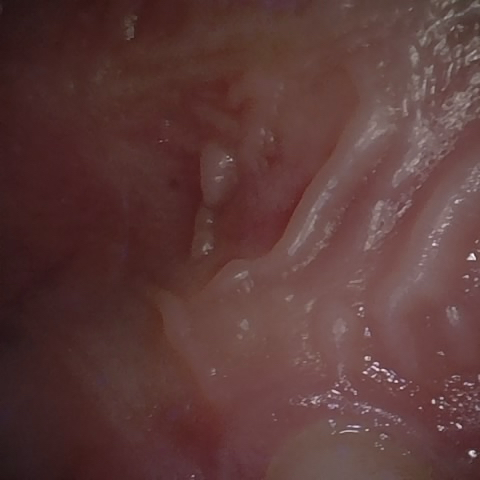

NHD30676

Annotated as "Good"

Original Image Rendering Image